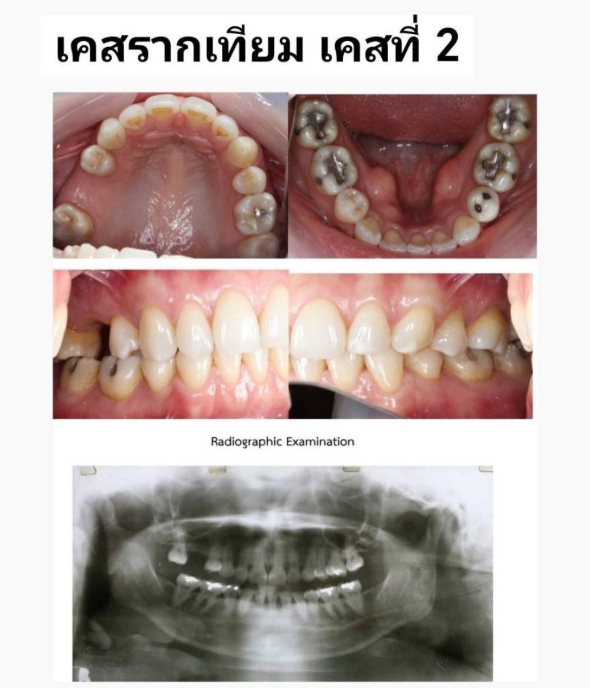

ตัวอย่างเคส